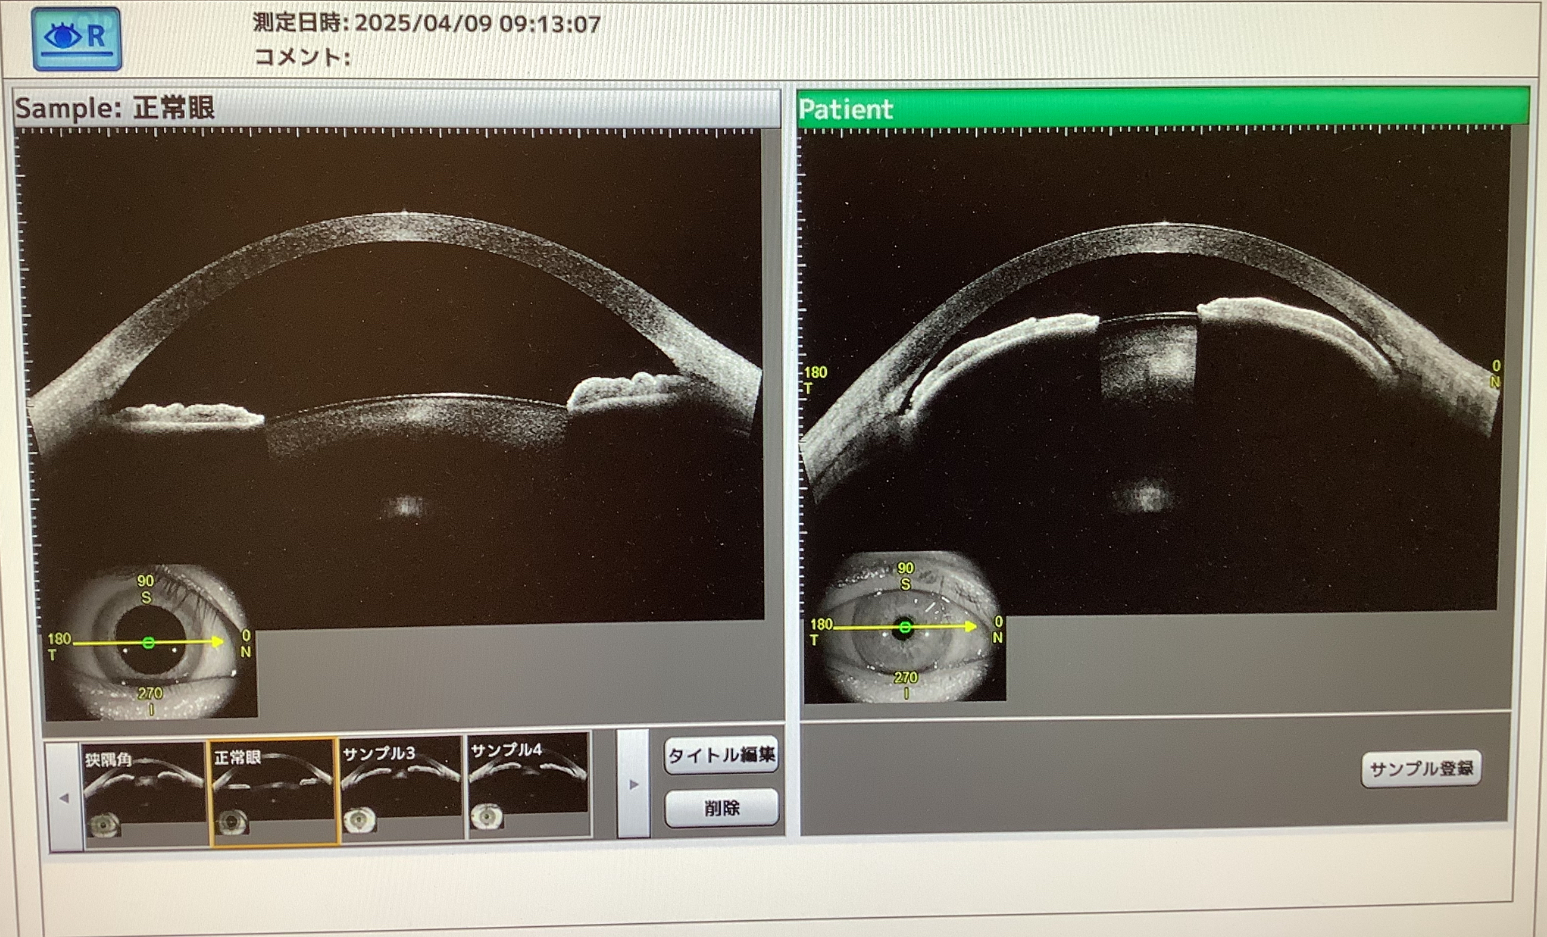

今日の手術では先月、左眼の急性緑内障発作を起こし、白内障の手術を行なった70代半ばの女性の方の右眼の手術がありました。緑内障発作の後の白内障手術は、チン小帯が弱くなっているために難しいことが多く、角膜も眼圧が上がって浮腫が起こった影響や前房が狭いので手術の侵襲が出やすく、術後の回復に時間がかかることがあるかと思います。この患者さんも手術前の視力が1.2あったのに、術後は一度、視力が下がり、術後1か月ほどしてようやく落ち着き、視力も0.8まで回復してきたところで、今日の手術になりました。

通常、左右で眼の作りは似ていることが多く、片眼に緑内障発作を起こした人は、もう一つの眼も緑内障発作を起こしやすい状態のことが多いかと思います。なので、基本的に急性緑内障発作を起こした眼のもう眼は発作予防のために早めに手術をするのが望ましいかと思っています。